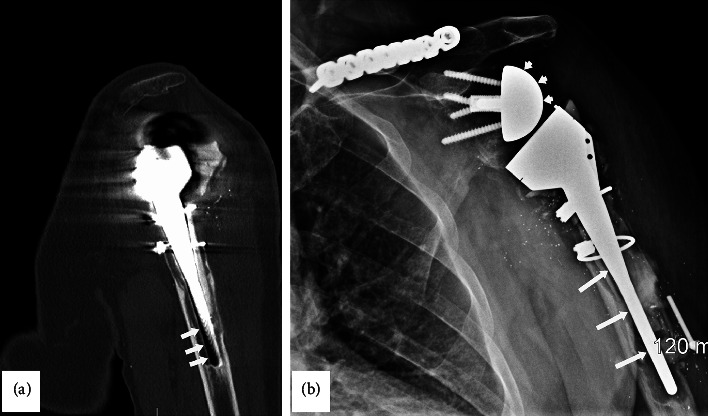

Gorham-Stout病(GSD),也被称为消失骨病或大量骨溶解,是一种罕见的疾病,其特征是骨基质破坏和血管结构增生导致骨吸收。虽然神经系统并发症,如继发于颅脑受累的脑脊液鼻漏和脊髓受累的截瘫已被报道,但周围神经并发症尚不清楚。我们描述了一个病例桡神经麻痹,这是一个医源性并发症的肩关节置换手术与骨丢失的肱骨类似GSD。患者为71岁男性,曾行左侧全肩关节置换术,12年后左侧上臂出现“骨突出”和疼痛。x光片显示肱骨近端未见。左上肢CT扫描显示肱骨部分松动,远端干周围明显骨溶解。患者接受了反向全肩关节置换术的翻修,并置换了肱骨头和肱骨干。患者术后出现左肩、左臂麻木、疼痛、无力及手腕下垂。体格检查显示腕、指背屈肌明显无力,肱桡肌消瘦无力,桡浅神经分布针刺感丧失。针刺肌电图显示指掌伸肌、肱桡肌和桡侧腕长伸肌的去神经支配改变。超声检查显示左侧桡神经螺旋沟肿大。EDX和US显示左桡神经在螺旋沟处麻痹。三角肌和肱三头肌肌电图异常轻微,提示臂丛后束受累。本病例说明了肩关节置换术后可能发生医源性桡神经麻痹,肱骨骨明显丢失,类似GSD。

Gorham-Stout disease (GSD), also known as vanishing bone disease or massive osteolysis, is a rare entity characterized by destruction of the osseous matrix and proliferation of vascular structures resulting in bone resorption. While neurological complications such as cerebrospinal rhinorrhea secondary to cranial involvement and paraplegia from spinal involvement have been reported, peripheral nerve complications are not known. We describe a case of radial nerve palsy that was an iatrogenic complication of shoulder replacement surgery with bone loss of the humerus resembling GSD. A 71-year-old male with a history of left total shoulder arthroplasty followed by a revision reverse total shoulder arthroplasty noted a "bone protruding" and pain in the left upper arm 12 years later. X-rays showed that the proximal portion of the humerus was not detectable. CT scan of the left upper extremity revealed loosening of the humeral component with prominent osteolysis most pronounced around the distal stem. The patient underwent a revision of the reverse total shoulder arthroplasty with replacement of the humeral head and shaft. He experienced numbness, pain, and weakness of the left shoulder and arm with wrist drop postoperatively. Physical exam revealed marked weakness of the dorsiflexors of the wrist and digits, wasting and weakness of the brachioradialis muscle, and loss of pinprick sensation of the superficial radial nerve distribution. Needle EMG showed denervation changes in the extensor digitorum communis, brachioradialis, and extensor carpi radialis longus muscles. An ultrasound (US) study showed enlargement of the left radial nerve at the spiral groove. The EDX and US findings suggested a left radial nerve palsy at the spiral groove. There were minimal EMG abnormalities in the deltoid and triceps muscles suggesting additional involvement of the posterior cord of the brachial plexus. This case illustrates the potential for iatrogenic radial nerve palsy following shoulder replacement surgery with significant bone loss of the humerus resembling GSD.